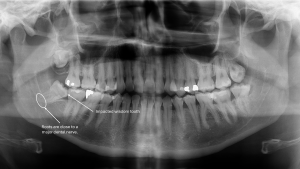

Helpful Hint: To see the patient experience in action, start by setting the patient age to 7 or under, then try 8 or older in the form below. This will demonstrate how the system tailors referrals for different age groups, enhancing care delivery for your patients.